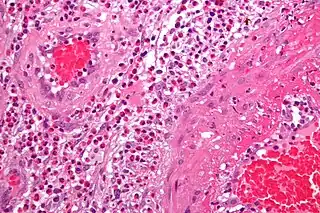

Vasculitis

La vasculitis engloba todos aquellos síndromes y enfermedades que cursan con inflamación de los vasos sanguíneos (vénulas, capilares y arteriolas de mediano y gran calibre) tanto de órganos específicos como generalizadas.[1][2]

Patogenia

Los dos mecanismos más conocidos por los que se produce una vasculitis son: